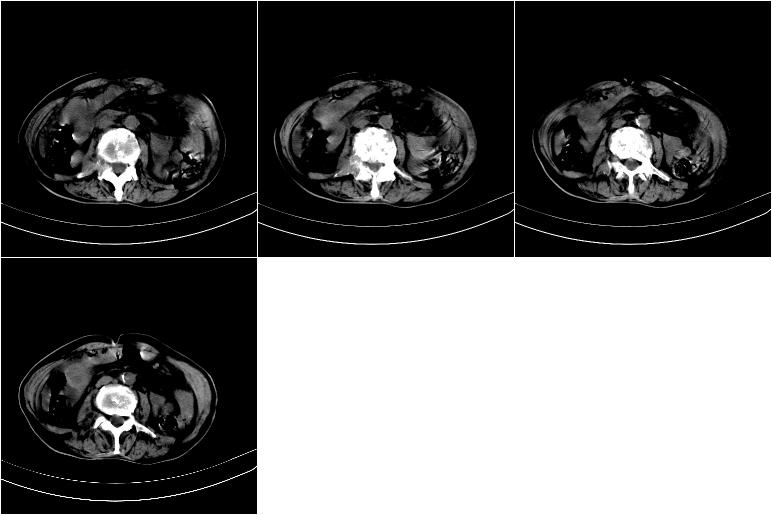

以下是引用奥特之父在2009-4-20 19:58:00的发言:[br]支持胰腺癌并转移性病变。